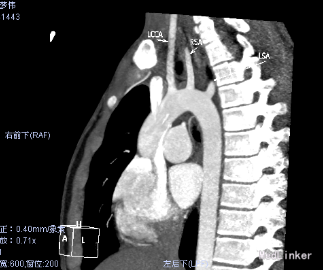

心脏CT:内脏、心房正位,左位心。肺动脉瓣二叶瓣,左室发育好。McGoon指数3.9。左室容积指数69.6ml/㎡。干下室间隔缺损,缺损约21.8mm。右位主动脉弓。迷走左锁骨下动脉。左锁骨下动脉异常起源于降主动脉起始处,经食管后方走行至左侧。左、右冠状动脉起源、走行未见异常。纵隔内未见体肺侧支动脉。气管下段中度狭窄。

患者因Fallot四联症行术前常规检查,发现合并迷走左锁骨下动脉。临床上迷走右锁骨下动脉比较多见。此患者右位主动脉弓。迷走左锁骨下动脉。左锁骨下动脉异常起源于降主动脉起始处,经食管后方走行至左侧。迷走左锁骨下动脉有二种类型:一种为单纯迷走锁骨下动脉,,一种同时合并Kommerell憩室。可能以22q11.2缺失有关。迷走左锁骨下动脉与双主动脉弓一样,是可以完整形成血管环的畸形。迷走左锁骨下动脉常合并有Fallot四联症、室间隔缺损等心脏畸形。心脏增强CT或核磁共振有助于左迷走锁骨下动脉诊断。通常没有食道、气管等脏器的压迫,不需要手术矫正。

先进的仪器设备给先天变异畸形的诊断带来了福音。右位主动脉弓伴迷走左锁骨下动脉很少伴发其他先天畸形,而右位主动脉弓伴镜面分支者则合并其他先天畸形多见。